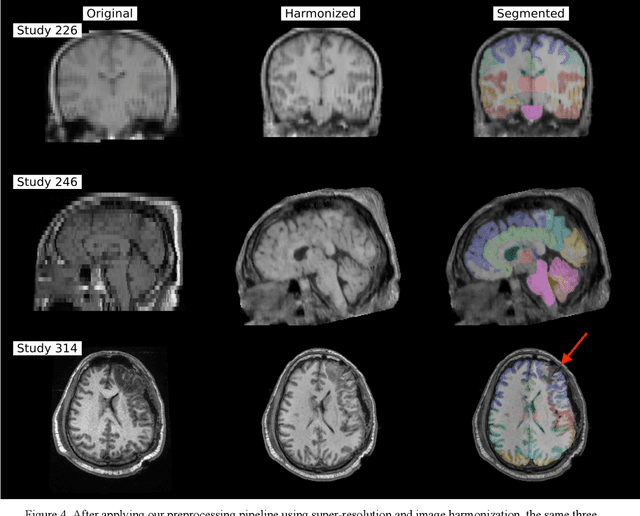

Abstract:Traumatic brain injury (TBI) is intrinsically heterogeneous, and typical clinical outcome measures like the Glasgow Coma Scale complicate this diversity. The large variability in severity and patient outcomes render it difficult to link structural damage to functional deficits. The Federal Interagency Traumatic Brain Injury Research (FITBIR) repository contains large-scale multi-site magnetic resonance imaging data of varying resolutions and acquisition parameters (25 shared studies with 7,693 sessions that have age, sex and TBI status defined - 5,811 TBI and 1,882 controls). To reveal shared pathways of injury of TBI through imaging, we analyzed T1-weighted images from these sessions by first harmonizing to a local dataset and segmenting 132 regions of interest (ROIs) in the brain. After running quality assurance, calculating the volumes of the ROIs, and removing outliers, we calculated the z-scores of volumes for all participants relative to the mean and standard deviation of the controls. We regressed out sex, age, and total brain volume with a multivariate linear regression, and we found significant differences in 37 ROIs between subjects with TBI and controls (p < 0.05 with independent t-tests with false discovery rate correction). We found that differences originated in 1) the brainstem, occipital pole and structures posterior to the orbit, 2) subcortical gray matter and insular cortex, and 3) cerebral and cerebellar white matter using independent component analysis and clustering the component loadings of those with TBI.